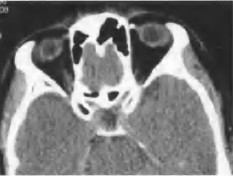

眼眶滑车骨化的CT表现

眼眶滑车骨化的CT征